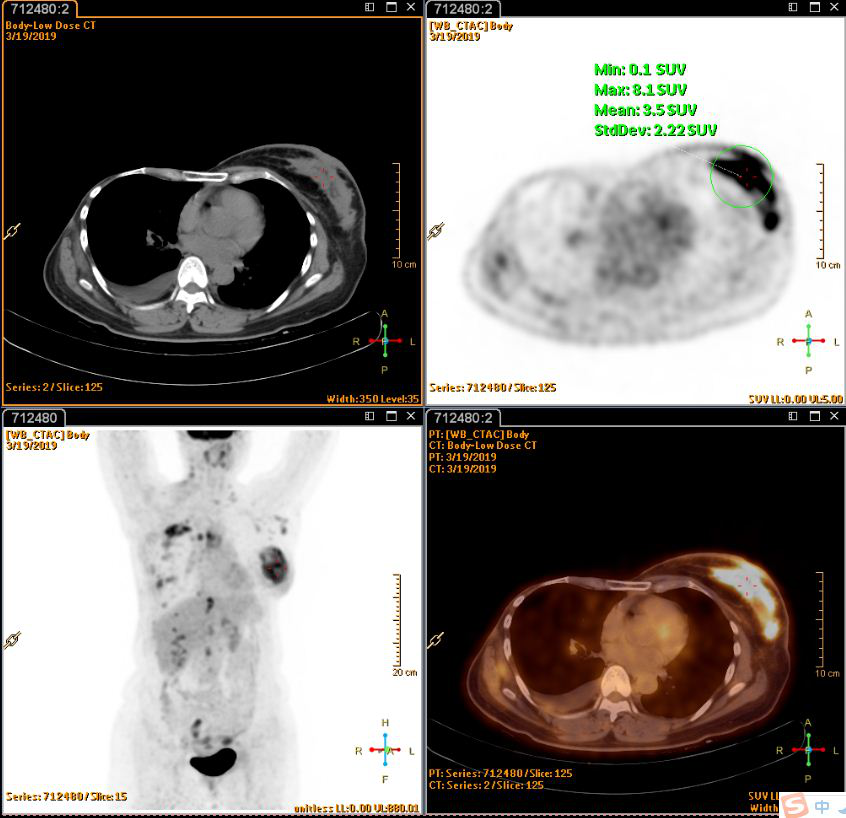

PET(2019-3-20):1.右乳癌术后改变,左侧乳腺腺体密实、左乳头周围皮肤增厚,葡萄糖代谢增高,考虑乳腺癌;颈部、纵隔、左侧腋窝、腹腔及腹膜后多发淋巴结转移,右侧胸膜转移,多发骨转移,多发肌肉转移;2.右侧液气胸,右肺炎症;肺下叶外基底段小结节,建议观察。

张1.png

图1